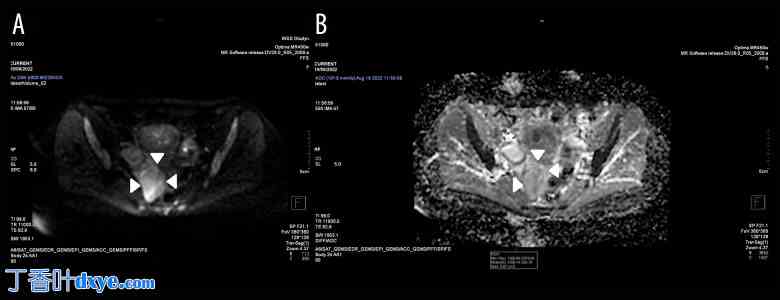

磁共振成像(MRI)显示,右侧卵巢后方(位于双侧子宫侧壁、阴道穹窿和直肠侧壁之间)腹膜后间隙内有一边界清晰、内部信号不均匀的病变肿块,内侧为髂内血管和梨状肌。肿块大小为71×37×67 mm。肿块边界清晰,呈蒂状,蒂部血管丰富,与双侧子宫后壁相连。T2加权像(T2WI)显示病灶内部信号不均匀,以高信号区为主(图1A、1B)。病灶内可见与肌组织(MT)信号强度相近的中低信号成分,呈分隔状和散在分布。T1加权像(T1WI)显示肿块大部分与肌组织呈等信号,可见少量低信号灶(图1C)。未见出血性改变或脂肪成分。注射对比剂(CA)Clariscan™钆特酸葡甲胺后,肿瘤呈明显强化;仅肿瘤内少量液体区域未见强化(图1D)。弥散加权成像(DWI)信号呈不均匀增高(图2A)。表观扩散系数(ADC)呈不均匀性;实性成分ADC值较低,但病灶信号总体较高,这可能提示细胞密度较低(图2B)。各感兴趣区域(ROI)的肿瘤ADC值介于2.979×10⁻³ s/mm²至1.306×10⁻³ s/mm²之间,平均值为2.258×10⁻³ s/mm²(图2B)。未见周围组织浸润(图1A-1D)。检查未发现淋巴结肿大。

图 2.

轴位扩散加权成像和表观扩散系数图。(A) 轴位扩散加权成像 (DWI) 显示高信号(b=800 s/mm²)。 (B)表观扩散系数(ADC)图显示ADC值为2.258×10−3s/mm2。